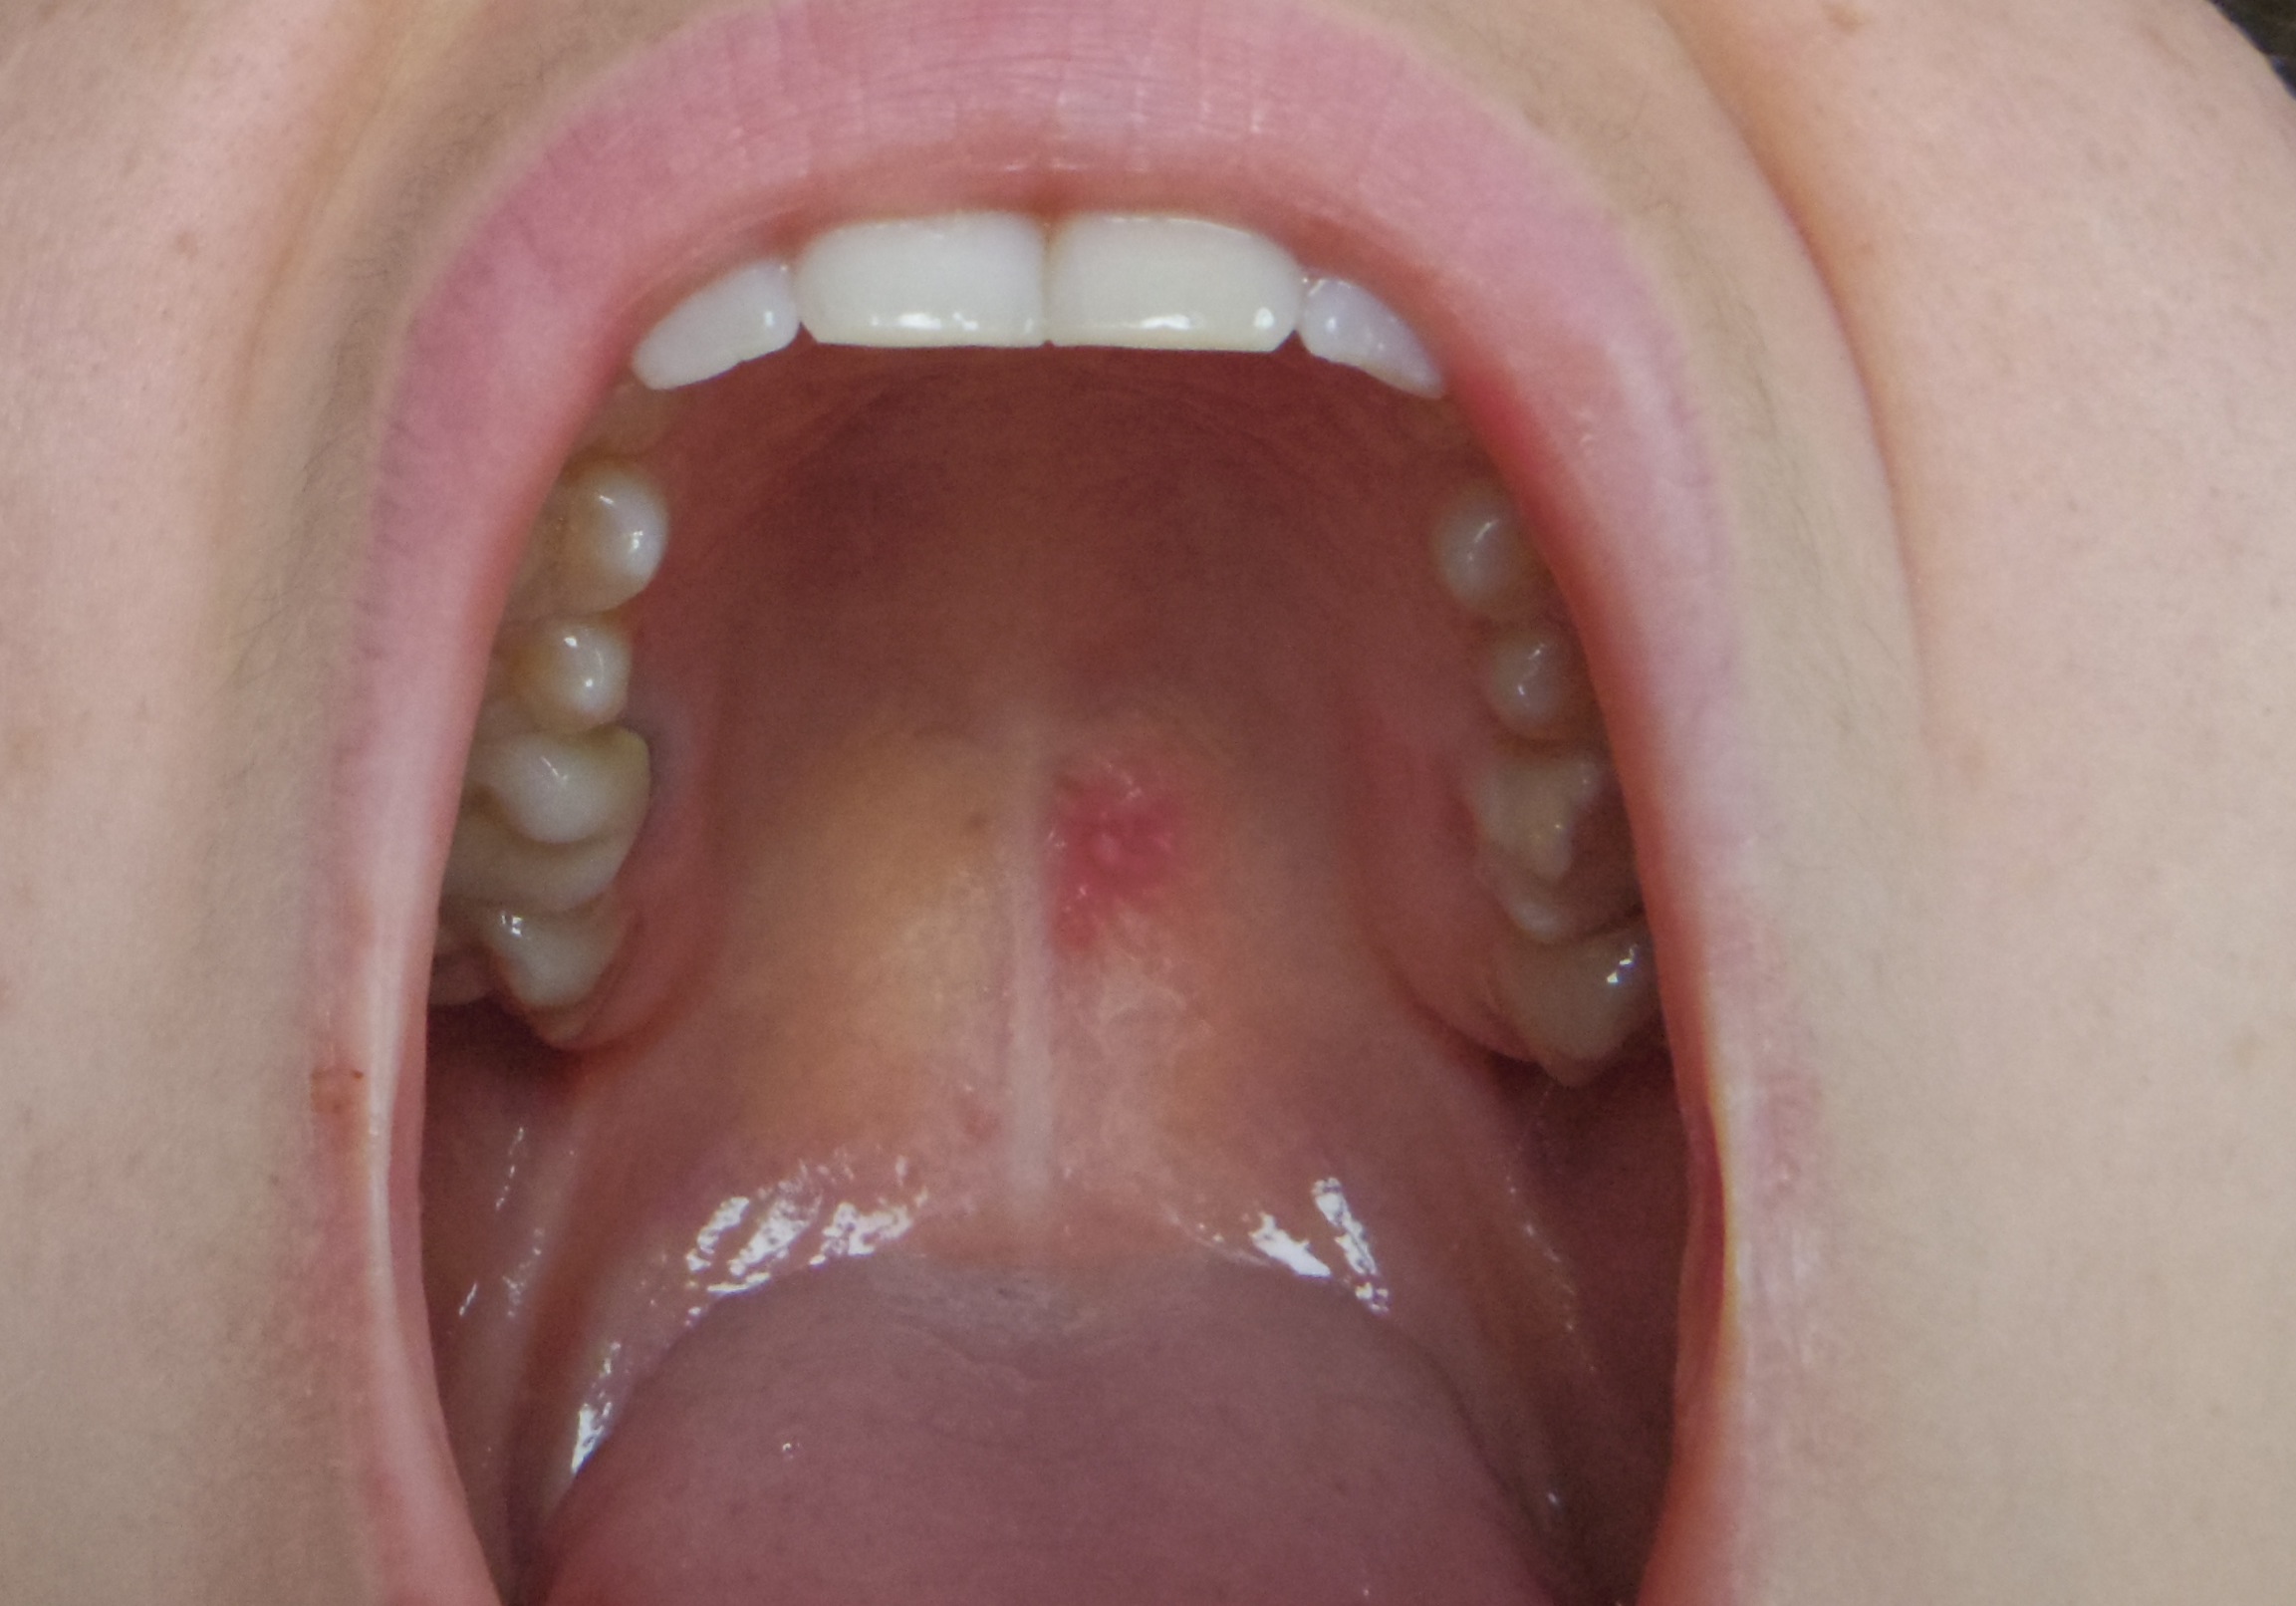

Tache Rouge Sur Le Palais Un Signe De Cancer

Tache Rouge Sur Le Palais Cancer S Forum Sante

Le Syndrome De La Fellation Vigoureuse Realites Biomedicales

Tache Rouge Palais Journal Des Femmes

Tache Rouge Au Palais Est Ce Un Aphte